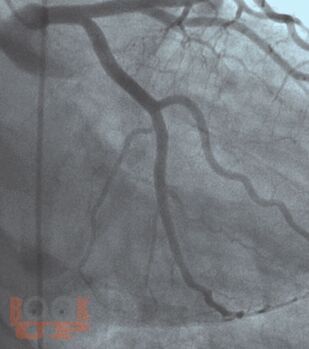

Основы ангиографии коронарных артерий

Книга предназначена для врачей клинических специальностей (кардиологов, терапевтов, врачей поликлинического звена и т.д.), которые регулярно направляют пациентов для проведения ангиографии коронарных артерий. В книге подробно освещены все необходимые правила подготовки пациентов к проведению исследования, детально рассказано о возможных осложнениях и методах их лечения. Книга способствует формированию у врачей алгоритма действий по самостоятельной оценке ангиограмм пациентов и их корректной интерпретации.